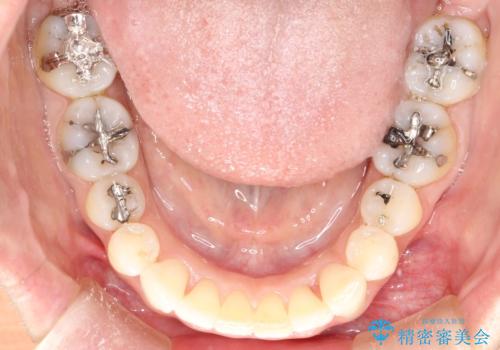

- 前歯のがたつきを気にされて来院されました。

右上の前から2番目の歯が前方に大きく傾いており、下の前歯もガタガタしていました。

インビザラインにて、歯と歯のあいだをわずかに削り並べる計画としました。

しっかりとマウスピースを使用していただけたので、順調に治療を終えることができました